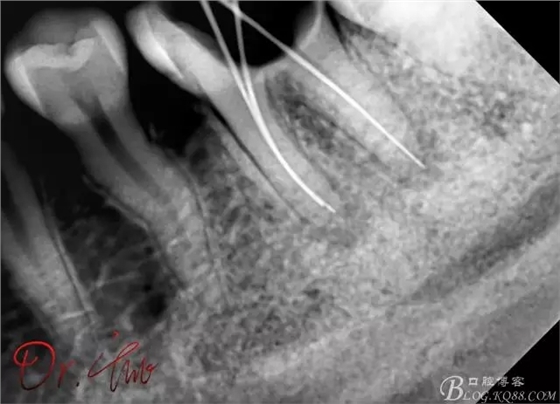

重點第二例病例,初診

拍片確定長度

試主尖,近中頰側(cè)形成臺階

試主尖,近中頰側(cè)再次拍片查看臺階位置及確定長度